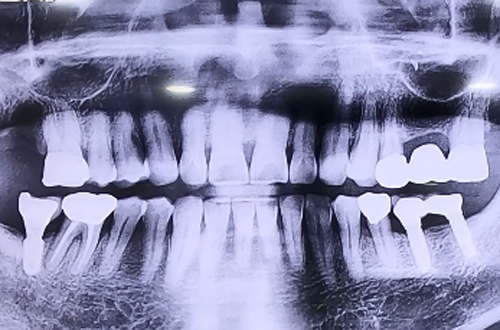

AFTER

뼈 이식 이후 뼈들이 흩어지지 않도록 차폐막을 덮어드리며 위쪽으로 잇몸을 꿰매어 마무리해 드렸습니다.

6개월이라는 기간을 충분히 기다렸다가 단단해진 뼈 위에 임플란트를 심고 윗 쪽으로 치아머리 부분 큰 어금니까지 예쁘게 완성할 계획입니다.

추후에 임플란트 수술이 진행되고 보철도 완성이 되면 다음 진료일지로 다시 찾아뵙도록 하겠습니다^^!